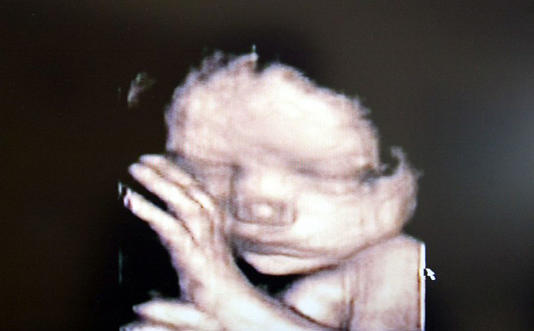

How the media mislead about Americans’ consensus on abortion Gallery How the media mislead about Americans’ consensus on abortion Contemplations, History 101, Last Days News, Recommended Reading How the media mislead about Americans’ consensus on abortion By kenpullen|2023-07-11T11:21:09-04:00July 11th, 2023|Contemplations, History 101, Last Days News, Recommended Reading| Read More 0